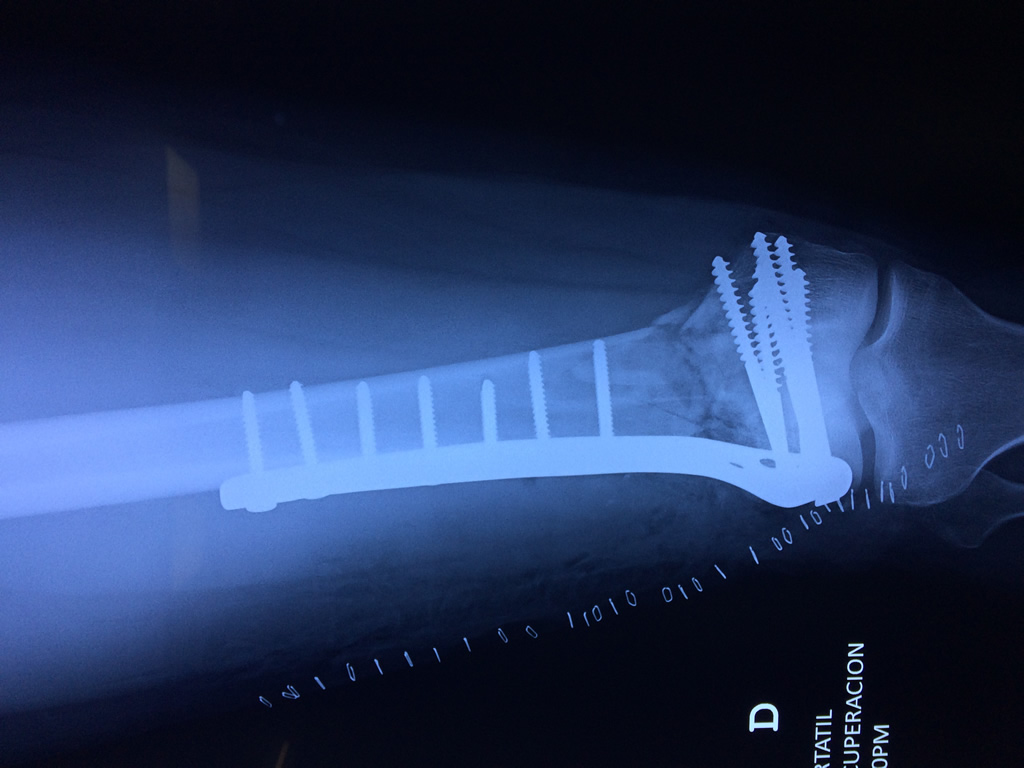

Cirugía de Rodillas

El fémur es el hueso del muslo, el segundo segmento del miembro inferior. Es el hueso más largo, fuerte y voluminoso del cuerpo humano.